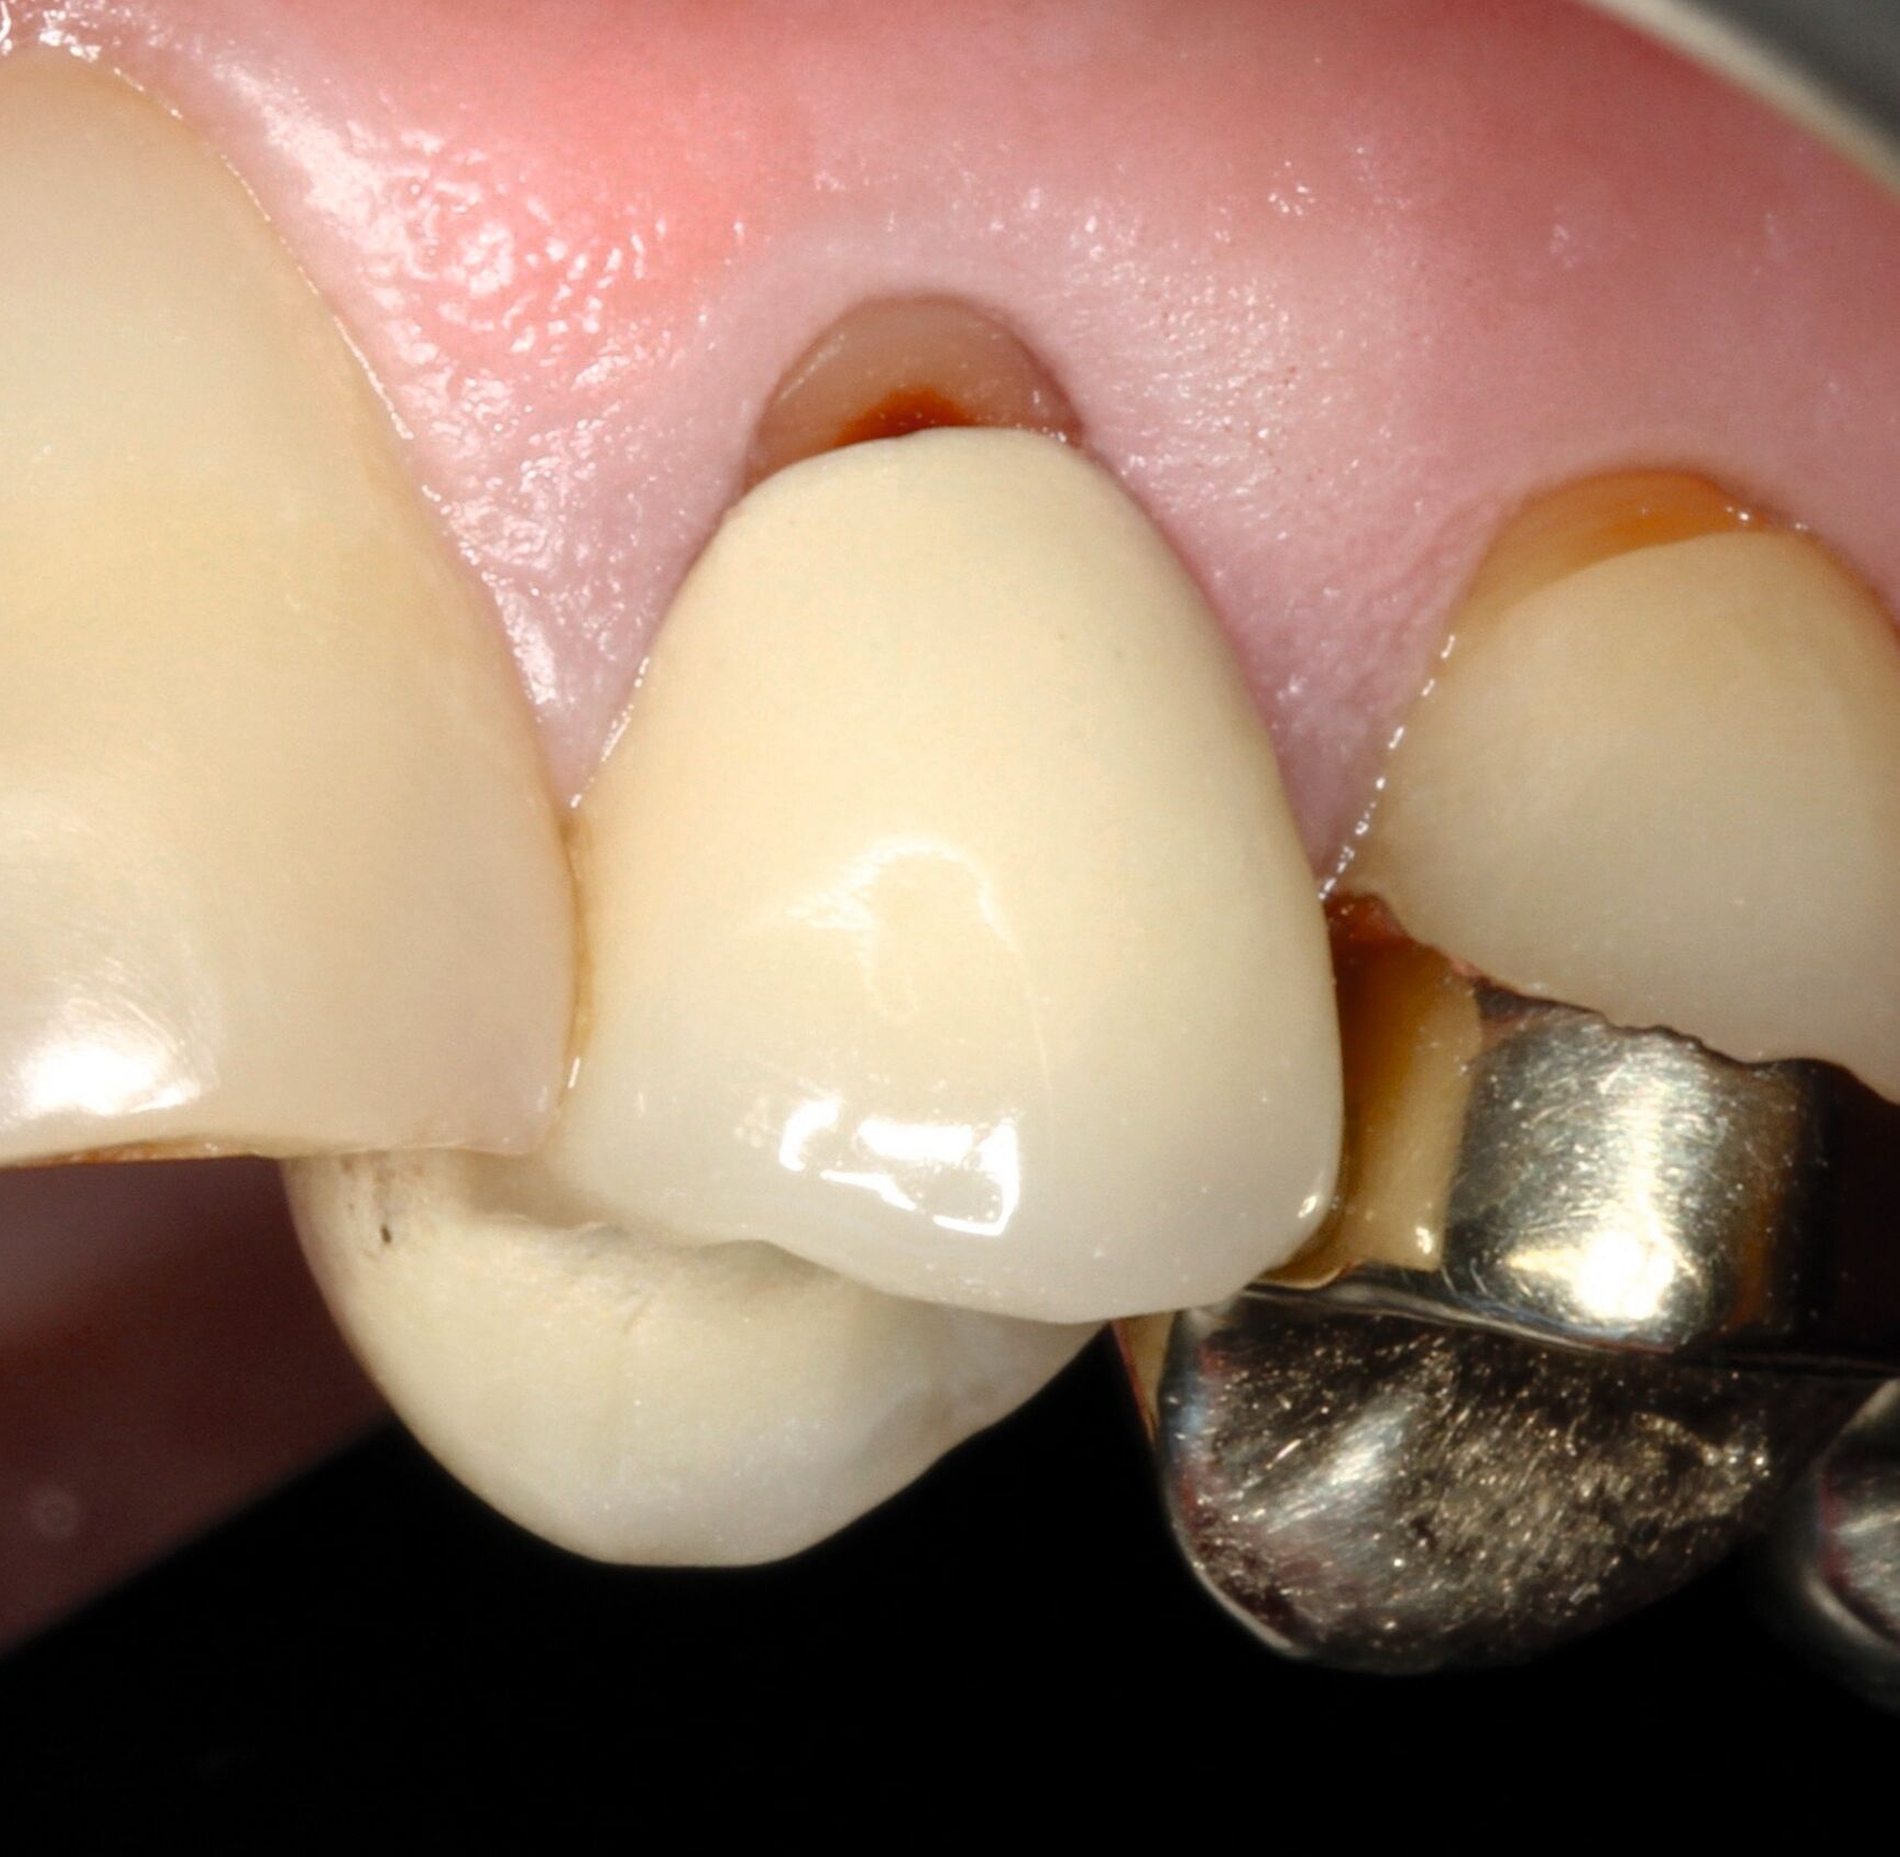

Die keilförmigen Defekte an den Zähnen 14 und 24 empfand der Patient bei Kontakt mit der Zunge als mechanische Irritationsstelle, weshalb eine Kompositreparatur zur Schonung der sonst intakten prothetischen Versorgung und der Zahnhartsubstanz eine sinnvolle und minimalinvasive Option darstellte [Jain et al., 2022]. Dabei wurden Retraktionsfäden zur Defektdarstellung eingebracht, die Dentinoberflächen mit einem Rosenbohrer mechanisch angeraut, die metallkeramischen Kronenränder mit CoJet-Sand silikatisiert, mit einem Silan silanisiert und die gesamte Restaurationsfläche mit einem 10-MDP-haltigen Universaladhäsiv vorbehandelt, um eine suffiziente Haftung zu generieren (Abbildungen 9 und 10) [Lührs, 2015; Stangel et al., 1987; Loguercio et al., 2015; Lührs et al., 2020; Ozcan und Niedermeier, 2002; Hickel et al., 2013]. Aufgrund der stark unterschiedlichen Transluzenz von Kronenmaterial und Komposit war es nicht möglich, eine unsichtbare Reparatur zu erzielen.